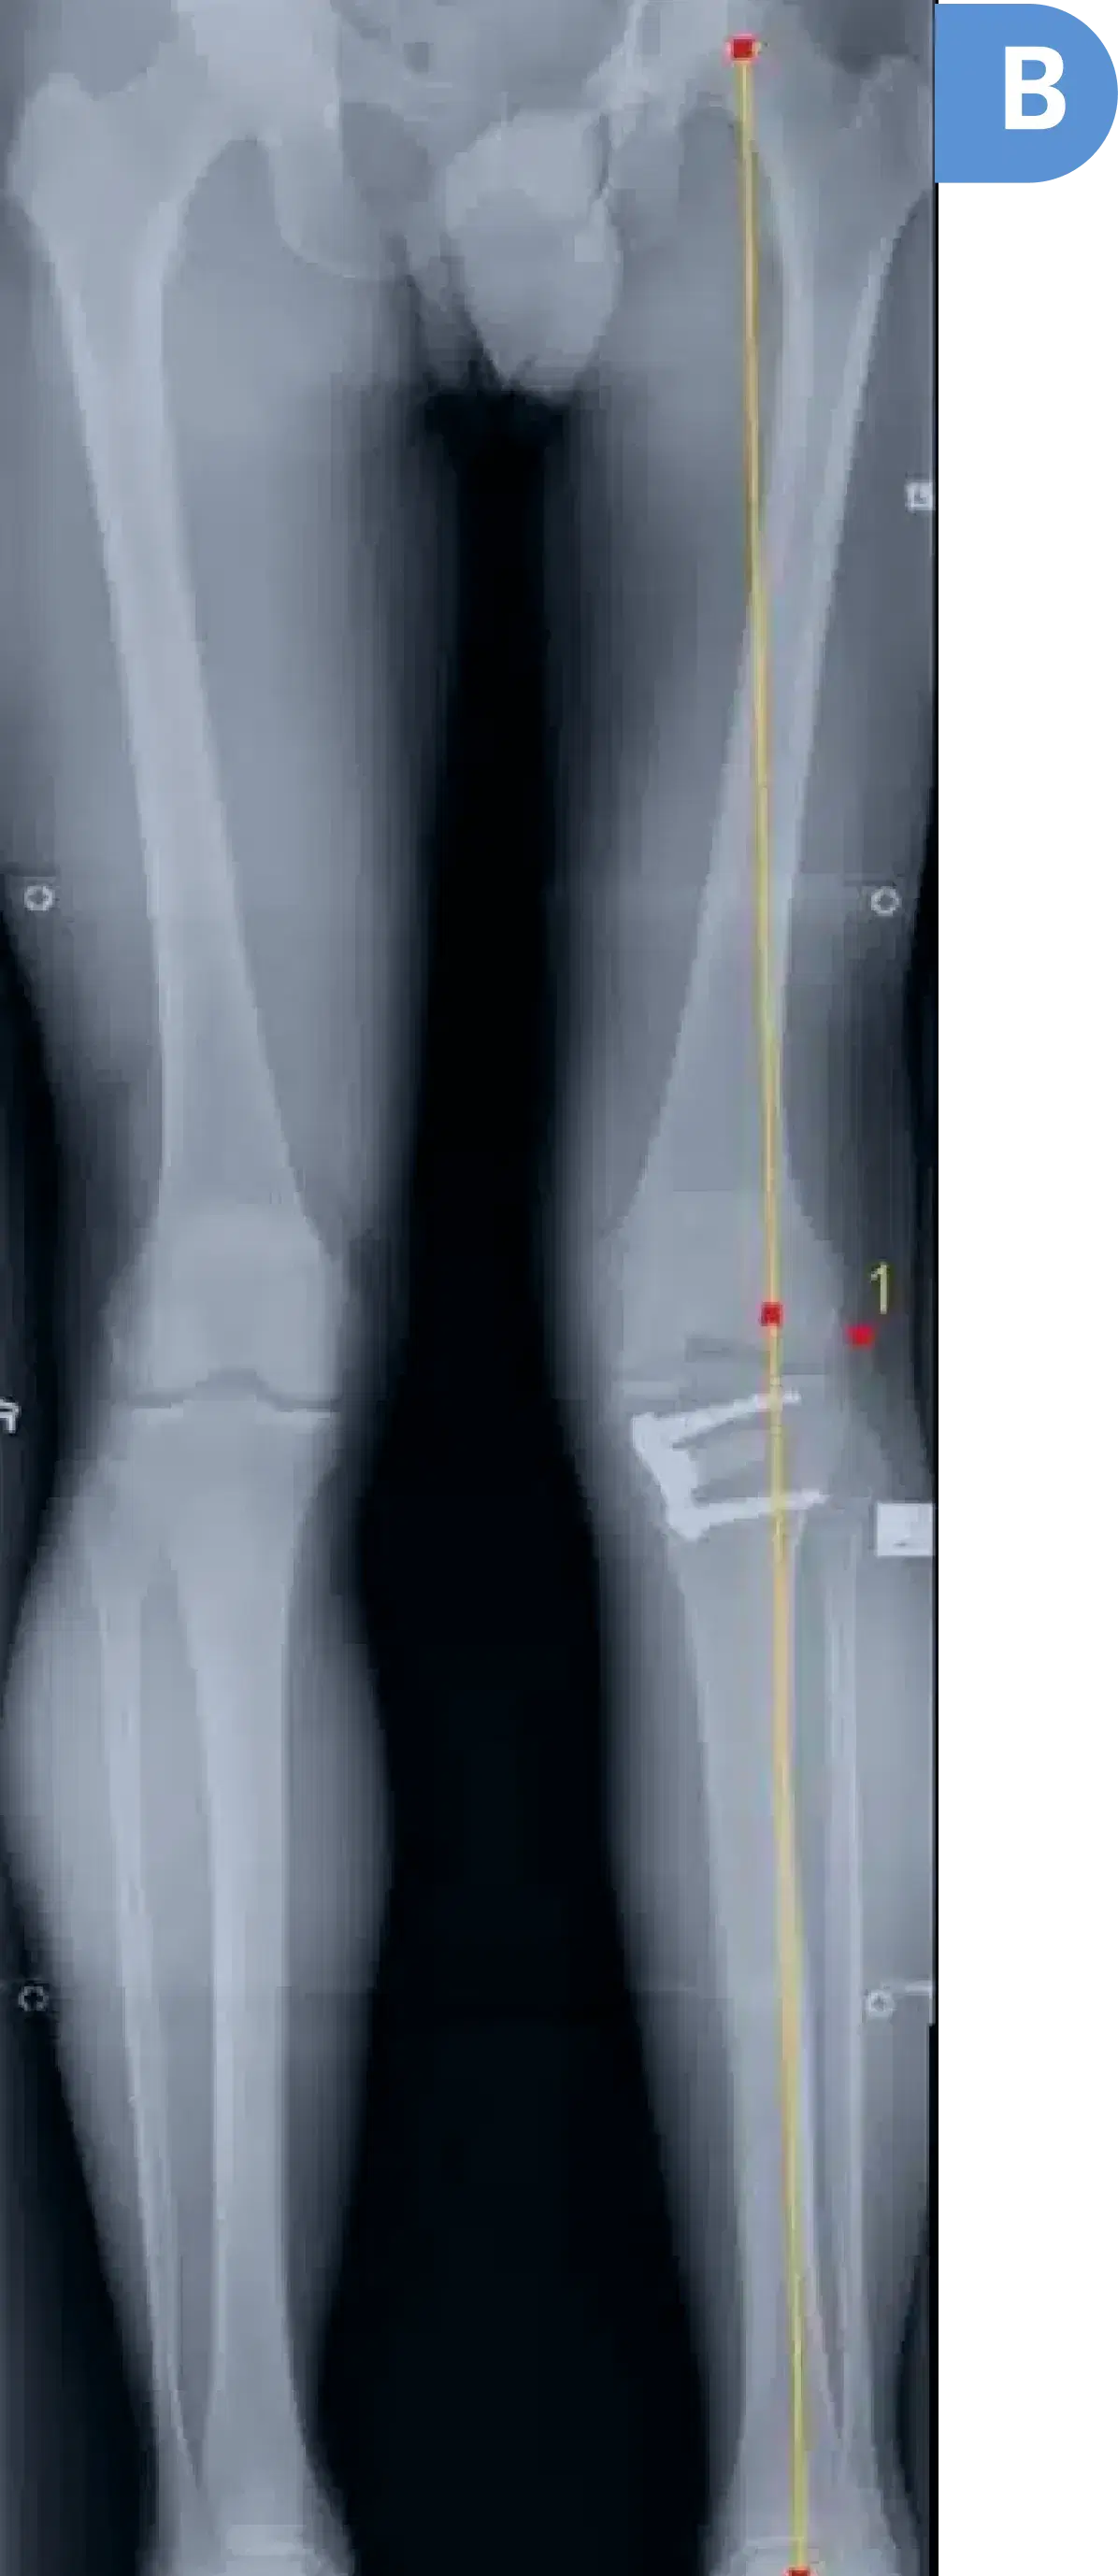

Post-surgery four-foot standing x-ray confirming correction of the axis into the normal outer side of the knee

B